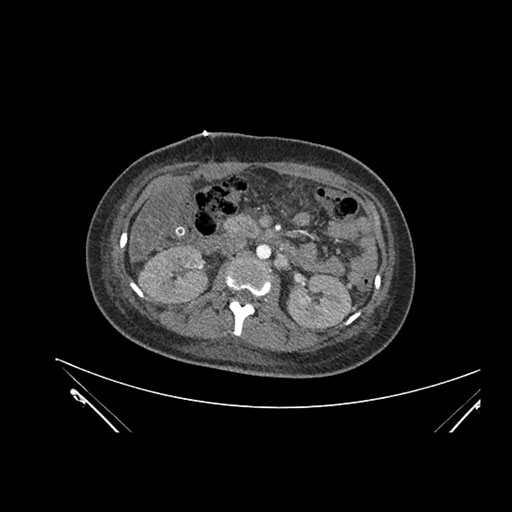

Axial Arterial

Axial Venous